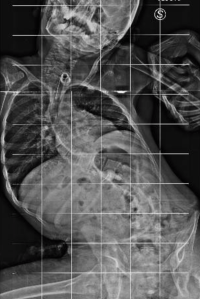

Qui di seguito, un esempio di un paziente affetto da scoliosi severissima, sottoposto a trattamento chirurgico.

Dopo l’intervento: